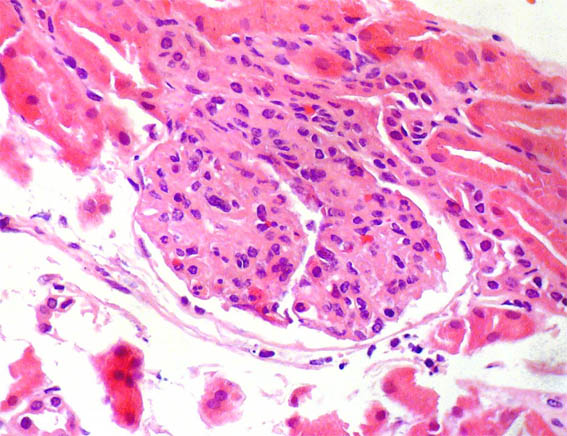

Figura 2.

H&E, X400.